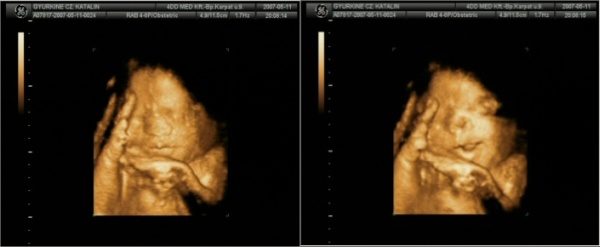

Samu úgy mocorog, mintha kiakarná szúrni a pocakomat.

Én nem számolom a mozgását, érzem én folyamatosan kisebb-nagyobb megszakításokkal.